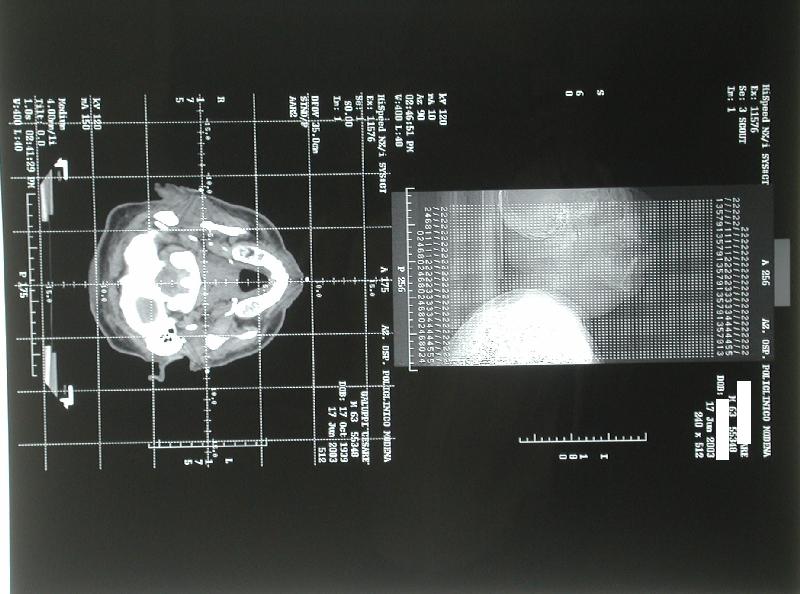

acceleratore lineare